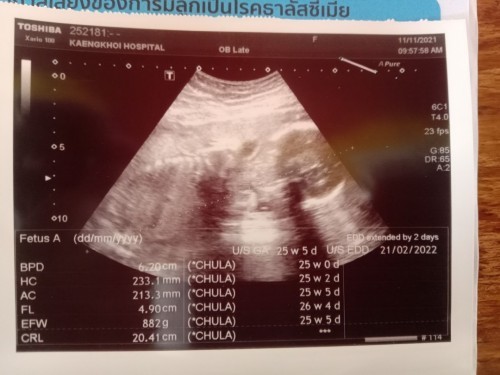

แม่ๆคนไหนคลอดกุมภา65มั้งค่ะน้ำหนักลูกตอนนี้ได้เท่ารัยกันแล้วแลกเปลี่ยนความรู้กันค่ะพึ่งไปซาว์มาวันนี้หมอบอกลูกตัวใหญ่เลยอยากถามแม่ๆว่าลูกน้ำหนักใกล้ๆกันมั้ย#ใครมีประสบการณ์ #ขอคำแนะนำหน่อยค่ะ #ขอบคุณล่วงหน้านะคะ

ไป u/s ล่าสุด 25 wks นน.น้องได้ 672 กรัม (ถ้าเทียบตามตารางนน.ปกติโดยเฉลี่ยของเด็ก จะประมาณ 660 กรัม)หมอบอกปกติโตตามเกณฑ์ดีค่ะ